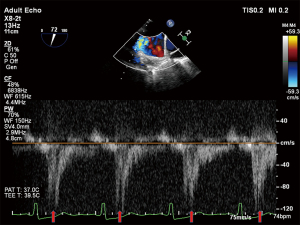

Twelve-lead electrocardiogram showed ST-T segment depression and signs of left ventricular hypertrophy. Transthoracic echocardiography (TTE) showed asymmetric septal hypertrophy with a maximal wall thickness of 16 mm at the LVOT level. Transesophageal echocardiography (TEE) revealed significant SAM of the anterior mitral leaflet (Figure 1, Video 1), causing dynamic LVOT obstruction (Figures 2,3) and severe MR (Figure 2, Video 2). On Valsalva maneuver, the LVOT pressure gradient reached 233 mmHg. Her left atrium was dilated and pulmonary artery systolic pressure was elevated. Reversed systolic wave was observed in the pulmonary vein flow (Figure 4). No abnormal muscle bundles were observed on imaging, including TEE and TTE.